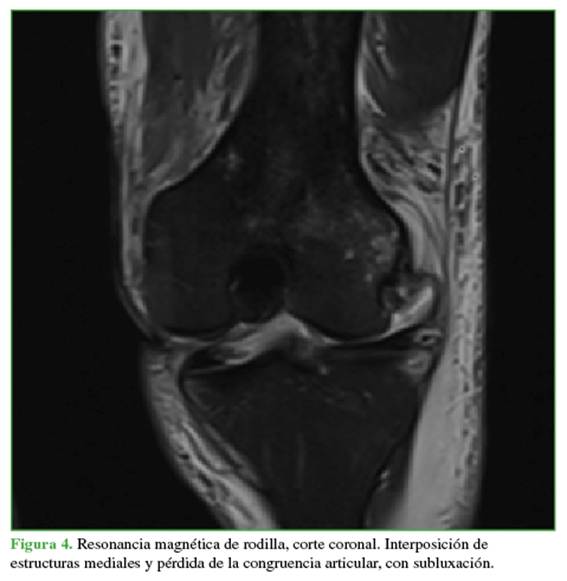

Las radiografías mostraban un aumento del espacio medial debido a la inestabilidad medial. Se ampliaron los estudios con una resonancia magnética (Figuras 4 y 5) para evaluar posibles tejidos o estructuras interpuestos y con una angiotomografía (Figura 6) para descartar una lesión vascular por el tiempo de evolución. Se observó un gran edema en los tejidos mediales, inclusive la cápsula y los tejidos mediales en la zona intercondílea, así como una persistente subluxación de la rodilla. Se descartó un compromiso vascular con integridad del paquete femoropoplíteo.

Aunque existen algunos casos descritos con desbridamiento o reducción artroscópica, la reducción abierta es el tratamiento de elección.19 En el caso presentado, se encontraron interpuestos el retináculo medial, las estructuras de la cápsula medial y el ligamento rotulofemoral medial, que también se visualizaron claramente, así como una porción importante del músculo vasto medial oblicuo distal. Hay varias estructuras que pueden quedar atrapadas en el espacio articular y evitar la reducción de la rodilla, entre ellas, el retináculo medial y las estructuras adyacentes son las más frecuentes. Otras causas de luxación irreductible de rodilla pueden ser una luxación intrarticular de la rótula o una luxación lateral de la rodilla con atrapamiento de la cápsula posterolateral en el compartimento lateral.